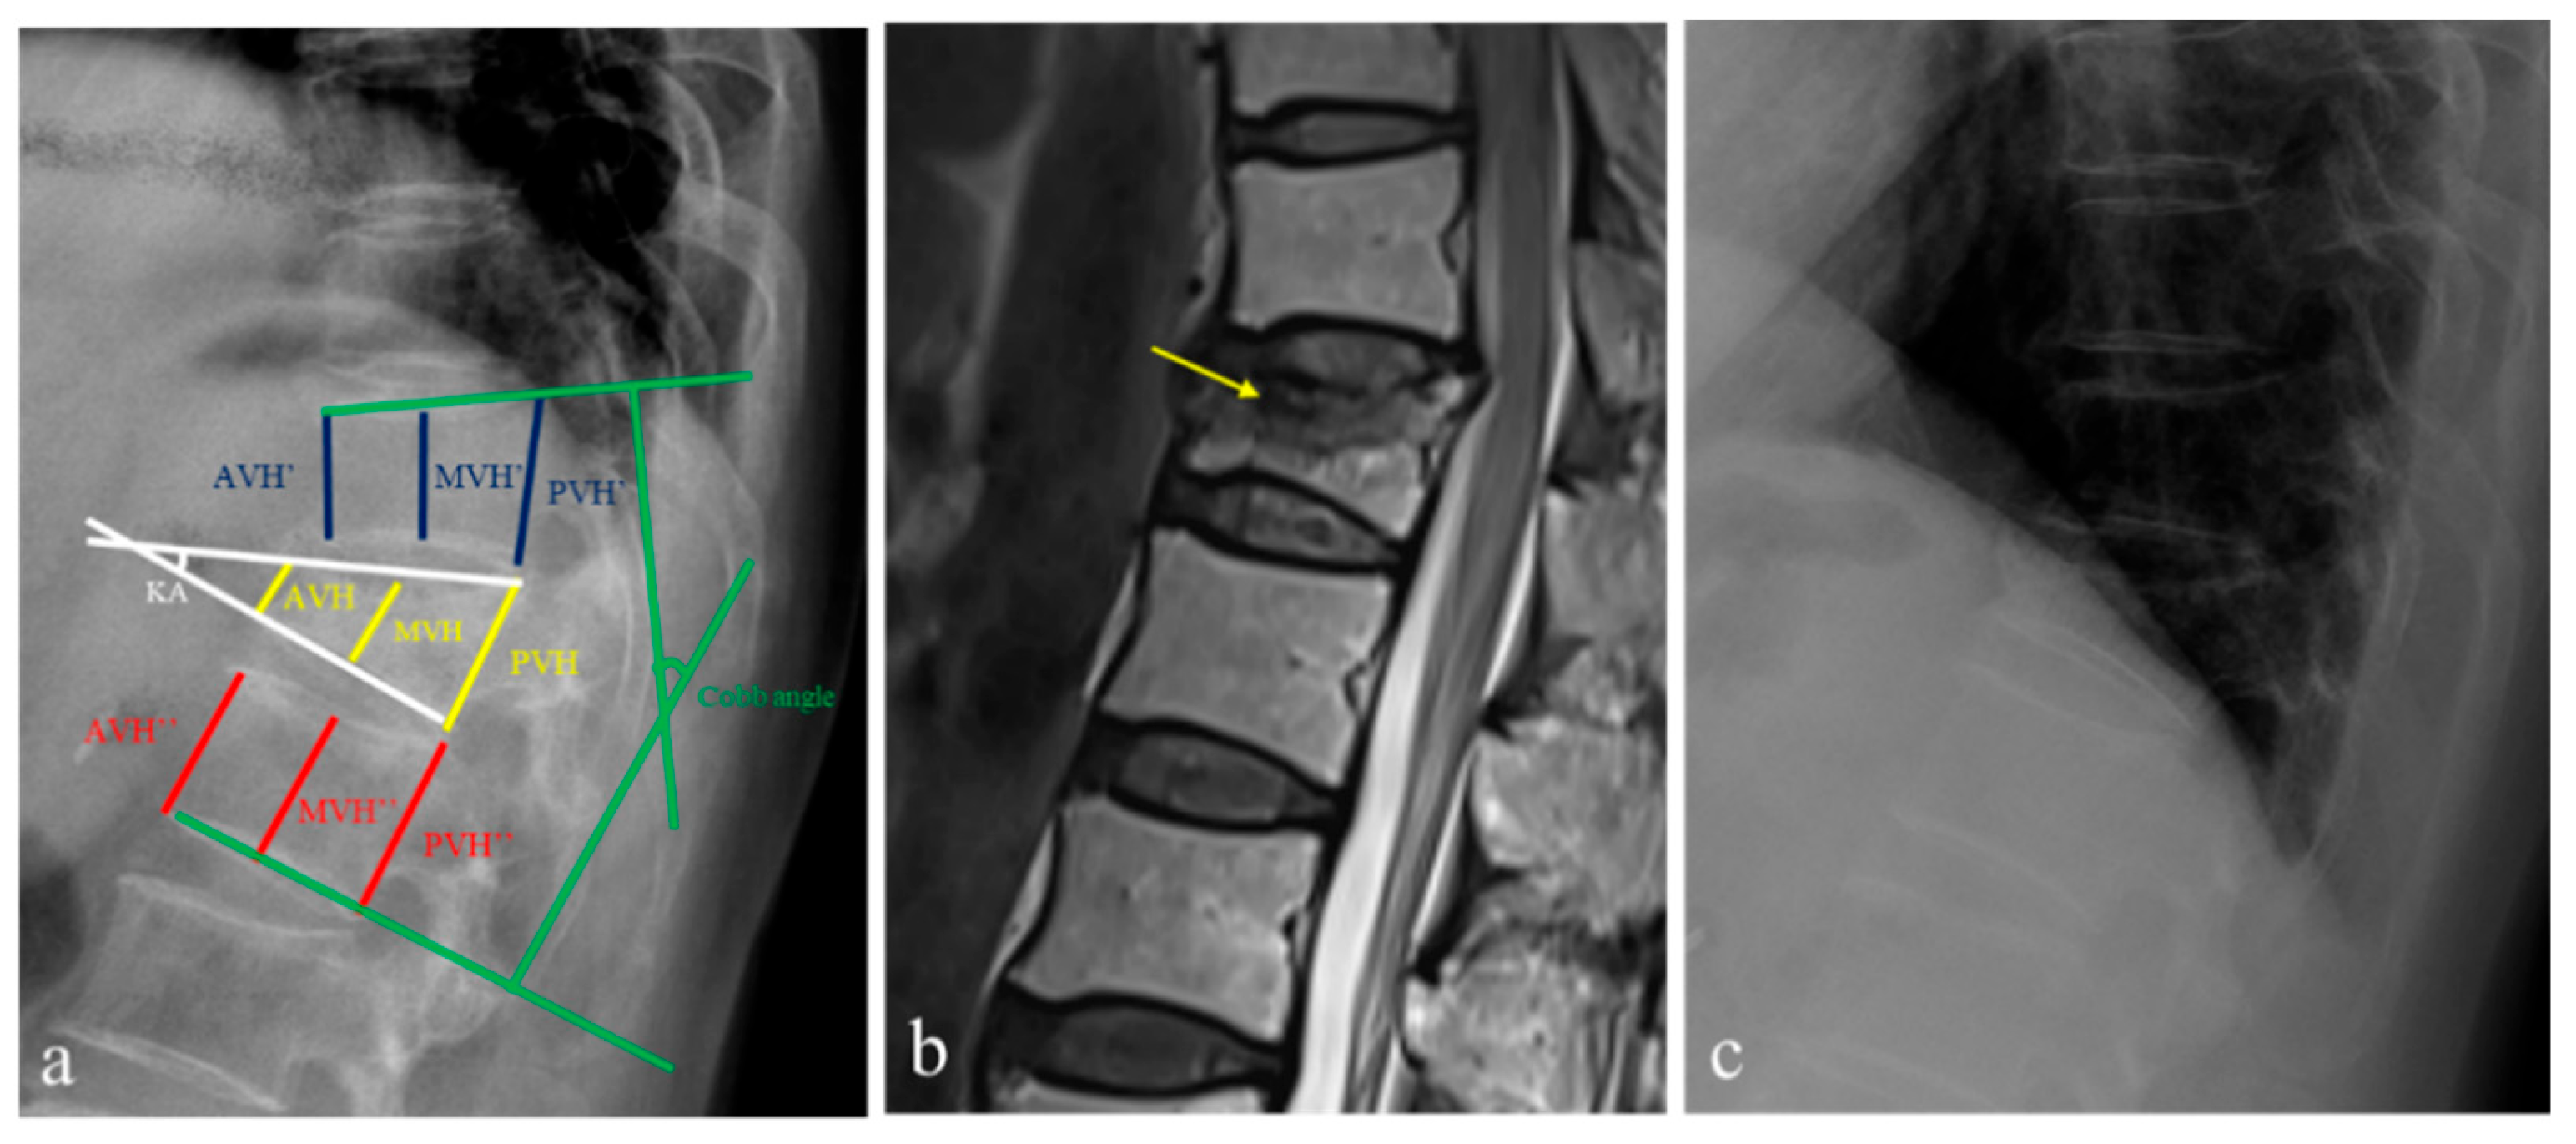

2. Materials and Methods

- Sadiqi, S.; Verlaan, J.J.; Lehr, A.M.; Chapman, J.R.; Dvorak, M.F.; Kandziora, F.; Rajasekaran, S.; Schnake, K.J.; Vaccaro, A.R.; Oner, F.C. Measurement of kyphosis and vertebral body height loss in traumatic spine fractures: An international study. Eur. Spine J. 2017, 26, 1483–1491. [Google Scholar] [CrossRef] [PubMed]

- Keynan, O.; Fisher, C.G.; Vaccaro, A.; Fehlings, M.G.; Oner, F.C.; Dietz, J.; Kwon, B.; Rampersaud, R.; Bono, C.; France, J.; et al. Radiographic measurement parameters in thoracolumbar fractures: A systematic review and consensus statement of the spine trauma study group. Spine 2006, 31, E156–E165. [Google Scholar] [CrossRef]

- Isomi, T.; Panjabi, M.M.; Kato, Y.; Wang, J.L. Radiographic parameters for evaluating the neurological spaces in experimental thoracolumbar burst fractures. J. Spinal. Disord. 2000, 13, 404–411. [Google Scholar] [CrossRef]

- Hsu, W.E.; Su, K.C.; Chen, K.H.; Pan, C.C.; Lu, W.H.; Lee, C.H. The Evaluation of Different Radiological Measurement Parameters of the Degree of Collapse of the Vertebral Body in Vertebral Compression Fractures. Appl. Bionics Biomech. 2019, 4021640. [Google Scholar] [CrossRef]